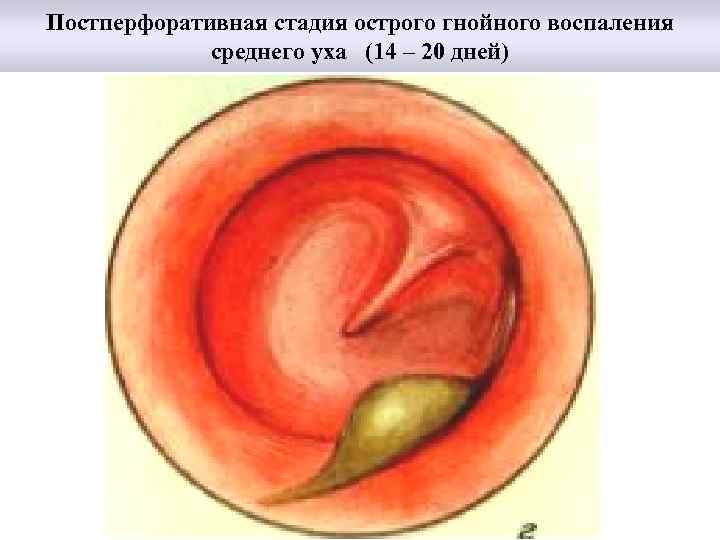

Постперфоративная стадия острого гнойного воспаления среднего уха (14 – 20 дней)